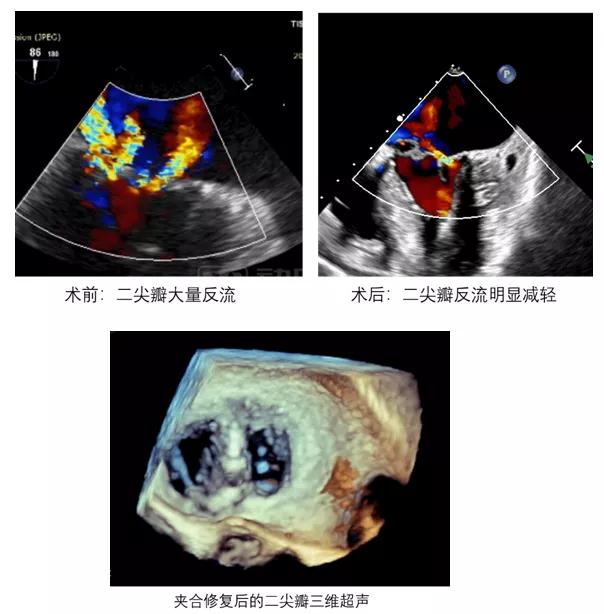

手术在经食道超声的引导下进行,无需正中开胸,无需体外循环,在心脏外科、心血管内科、麻醉科、手术室的共同努力下,仅仅在患者左侧肋间一个4厘米的小口,凌云鹏主任使用特制的夹合装置将脱垂的瓣叶重新夹合到了瓣环平面,关键操作耗时不到一小时,手术全程几乎无出血。术后复查超声心动显示,患者的二尖瓣反流明显减轻。